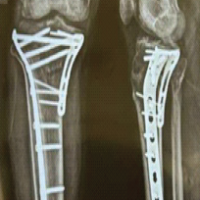

Fracture reduction was achieved under direct vision with manual manipulation and aided by K-wires or small reduction forceps as required. Intraoperative fluoroscopy was used to confirm restoration of the volar tilt, radial height, and radial inclination.

An anatomically contoured volar locking/non-locking compression plate was then applied proximal to the watershed line. The distal screws were inserted first to achieve subchondral fixation, followed by proximal cortical screws. Final reduction and implant placement were confirmed under fluoroscopy in both anteroposterior and lateral views.

Clinical examination for CTS symptoms (numbness, tingling, night pain) was performed at 3 and 6 months. Electromyogram/nerve conduction velocity (EMG/NCV) studies were used to confirm clinical diagnosis. Functional assessment was done using the PRWE score as mentioned in Fig. 1.

Figure 1: Post-operative protocol.